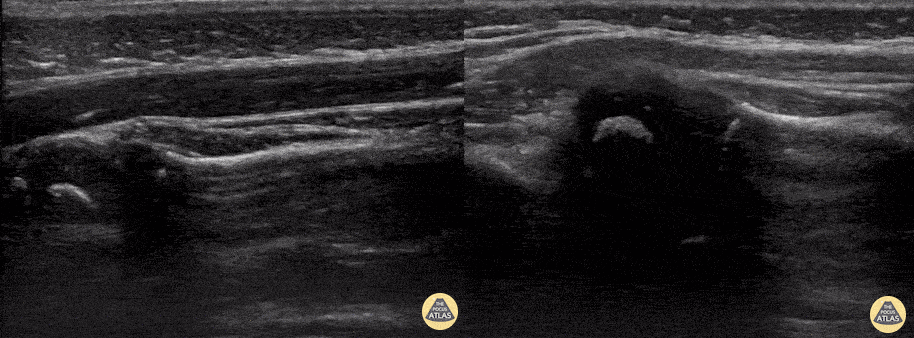

2-year-old female was brought to the ED refusing to use her left arm after her father caught her by the arm to prevent her falling down flight of stairs. POCUS was performed to confirm clinical suspicion of a Nursemaid’s elbow (or radial head subluxation). The left image reveals classic findings of a Nursemaid’s elbow including widening of the synovial fringe and inward extension of the annular ligament. Further, you can appreciate both the supinator muscle, as well as the annular ligament are being pulled into the joint space, a finding known as hook sign. The image on the right is the post-reduction image showing normal alignment and contour of the annular ligament. Austin Meggitt, MD Pediatric Emergency Ultrasound Fellow Denver Health Medical Center @DenverEMed